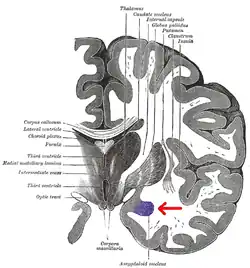

Cuerpo amigdalino

El cuerpo amigdalino, complejo amigdalino o amígdala cerebral es un conjunto de núcleos de neuronas localizadas en la profundidad de los lóbulos temporales de los vertebrados complejos, incluidos los humanos.[1] La amígdala forma parte del sistema límbico, y su papel principal es el procesamiento y almacenamiento de reacciones emocionales.[2][3]

Las regiones descritas como «amígdala» en realidad abarcan una serie de núcleos con distintos atributos funcionales llamada complejo amigdalino. Entre esos núcleos se encuentra el grupo basolateral, el núcleo centromedial y el núcleo cortical. El grupo basolateral se puede dividir a su vez en el núcleo lateral, el basal y los núcleos basales accesorios.[2][4]